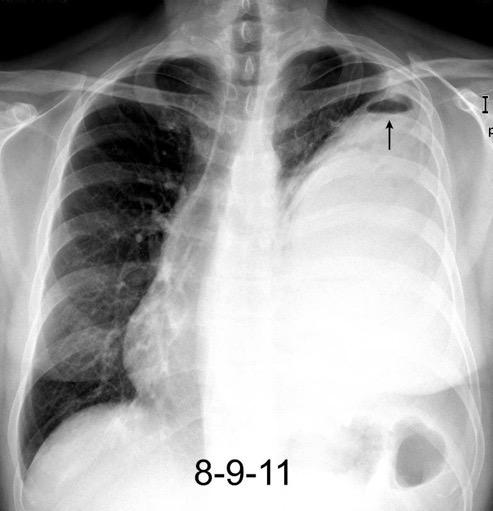

Marzo 2014: Perforación longitudinal distal secundaria a episodio de vómito (síndrome de Boerhaave). Derrame pleural izdo. que evoluciona a empiema.

Wang C-T et al. Tension hydropneumothorax in a Boerhaave syndrome patient: A case report . World J Emerg Med, 2021. Katabathina V et al. Nonvascular, nontraumatic mediastinal emergencies in adults:a comprehensive review of imaging findings. Radiographics. 2011.